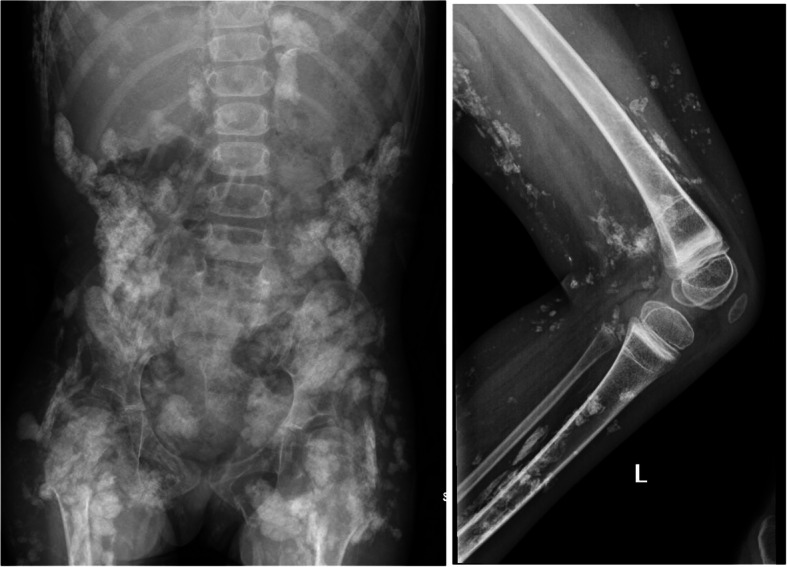

Calcinosis is a severe manifestation of juvenile and adult idiopathic inflammatory myopathies, which can lead to pain, limited range of motion, disfigurement, and infection. It is more common in juvenile idiopathic inflammatory myopathies, especially in juvenile dermatomyositis (JDM). Calcinosis can be visible on cutaneous surfaces, although can also present in muscles and internal organs, making a thorough assessment difficult without imaging modalities. In this narrative review, we discuss different imaging modalities used in evaluating JDM-associated calcinosis including X-ray, computed tomography (CT), magnetic resonance imaging (MRI), and ultrasound (US).